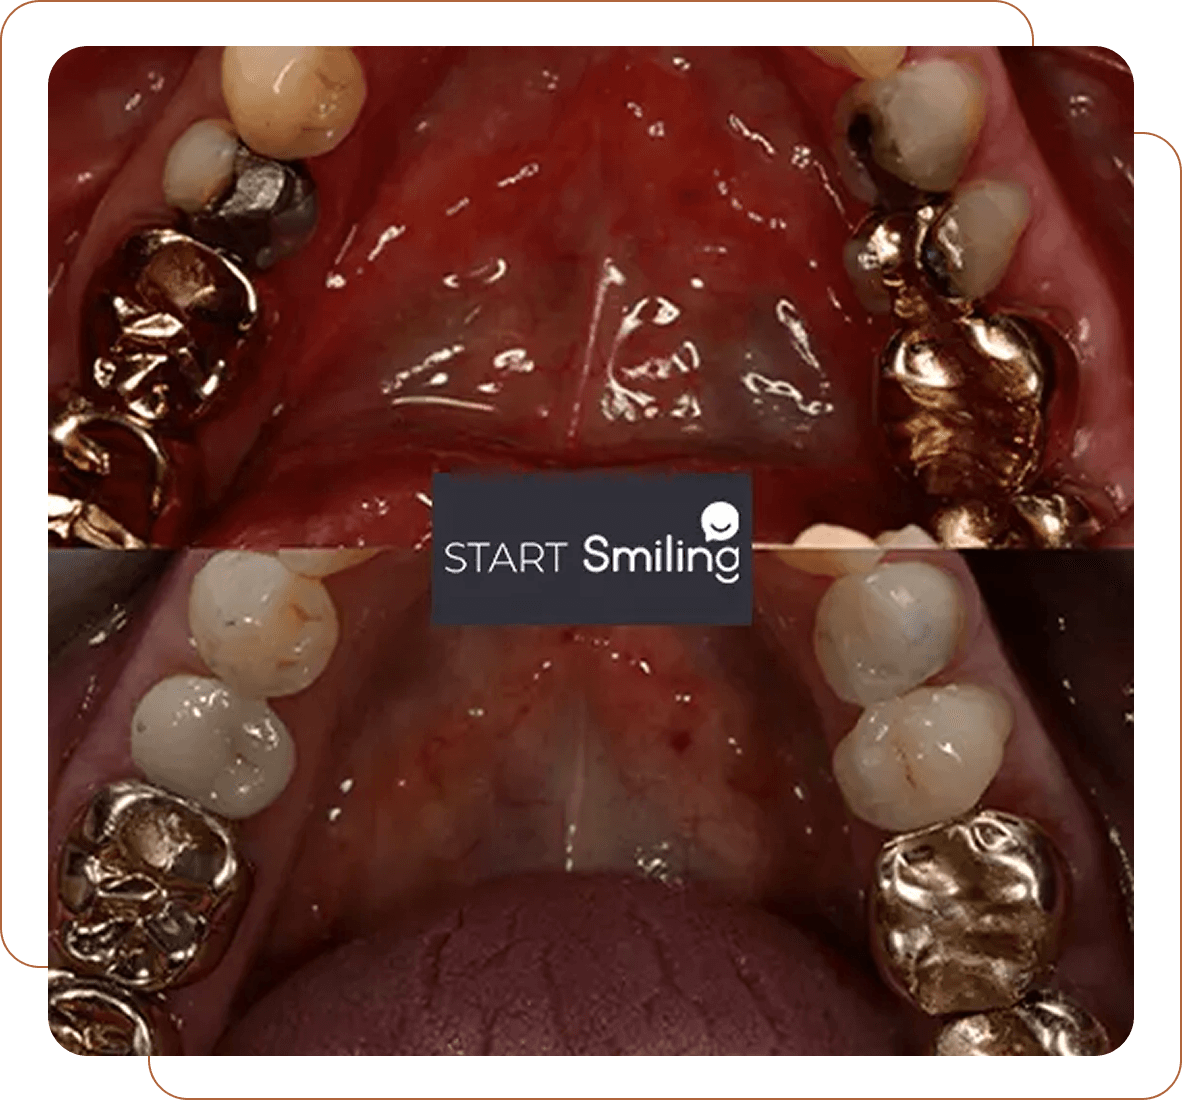

Smile Gallery